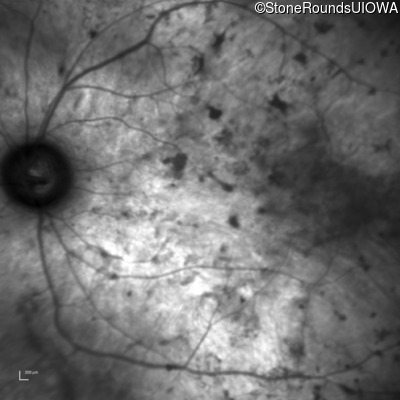

Infrared Fundus Photograph - Left - Light Perception

Exemplar